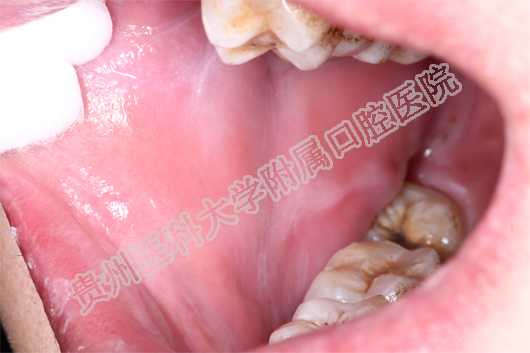

(患者治疗前后的口腔黏膜病损对比 上图:治疗前 下图:治疗1周后)

当天值班的王珣主治医师为小邓这一特殊病人加号,并作了相关检查后诊断小邓为药物引起的“过敏性口炎”。王珣医师介绍:小邓来的时候已经很严重了,上下唇、手背、拇指已经出现红色斑块,并且全口黏膜溃烂、生殖器可见不规则糜烂面。像小邓这种情况根本无法进食、而且疼痛难忍。若不及时救治,很有可能造成电解质紊乱。随后王珣医生询问病史发现:原来,5天前,小邓因智齿冠周炎自行服用了“消炎片”,随后出现全口黏膜溃烂,无法进食而且说话都困难,随后皮肤上也起红斑,生殖器也开始溃烂,疼痛难耐,无法入睡,人也明显消瘦了许多。

王珣医师嘱患者停用可疑药物,并为他对症用药。由于“过敏性口炎”的病情发展变化较大,王珣医生还为患者留了自己的微信,以便实时了解小邓的病情变化。1周后,小邓复诊时口腔生殖器黏膜已经痊愈,上下唇及手背、拇指的斑块也基本消退。小邓非常感谢91直播